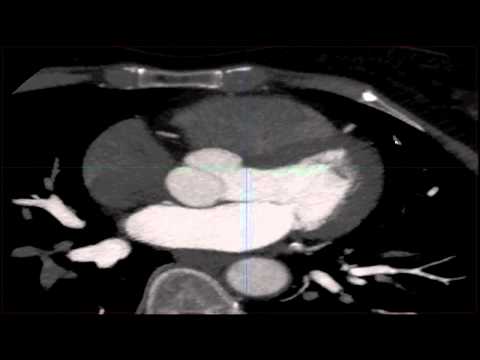

Image obtained without the threshold set to color the calcium pink.

Image obtained without the threshold set to color the calcium pink. The american journal of medicine. A coronary calcium scan is a ct scan of your heart that detects and measures the amount of a coronary calcium scan uses a special scanner such as an electron beam ct or a multidetector ct. Image obtained without the threshold set to color the calcium pink.